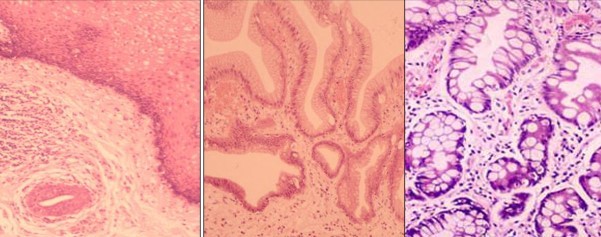

What is 1,2 and 3?

What changes lead to cancer?

Metaplastic glandular epithelium (intestinal type)

Dysplasia changes showing some of the cytological and histological features of malignancy but no invasion through the basement membrane

Adenocarcinoma invasion through the basement membrane